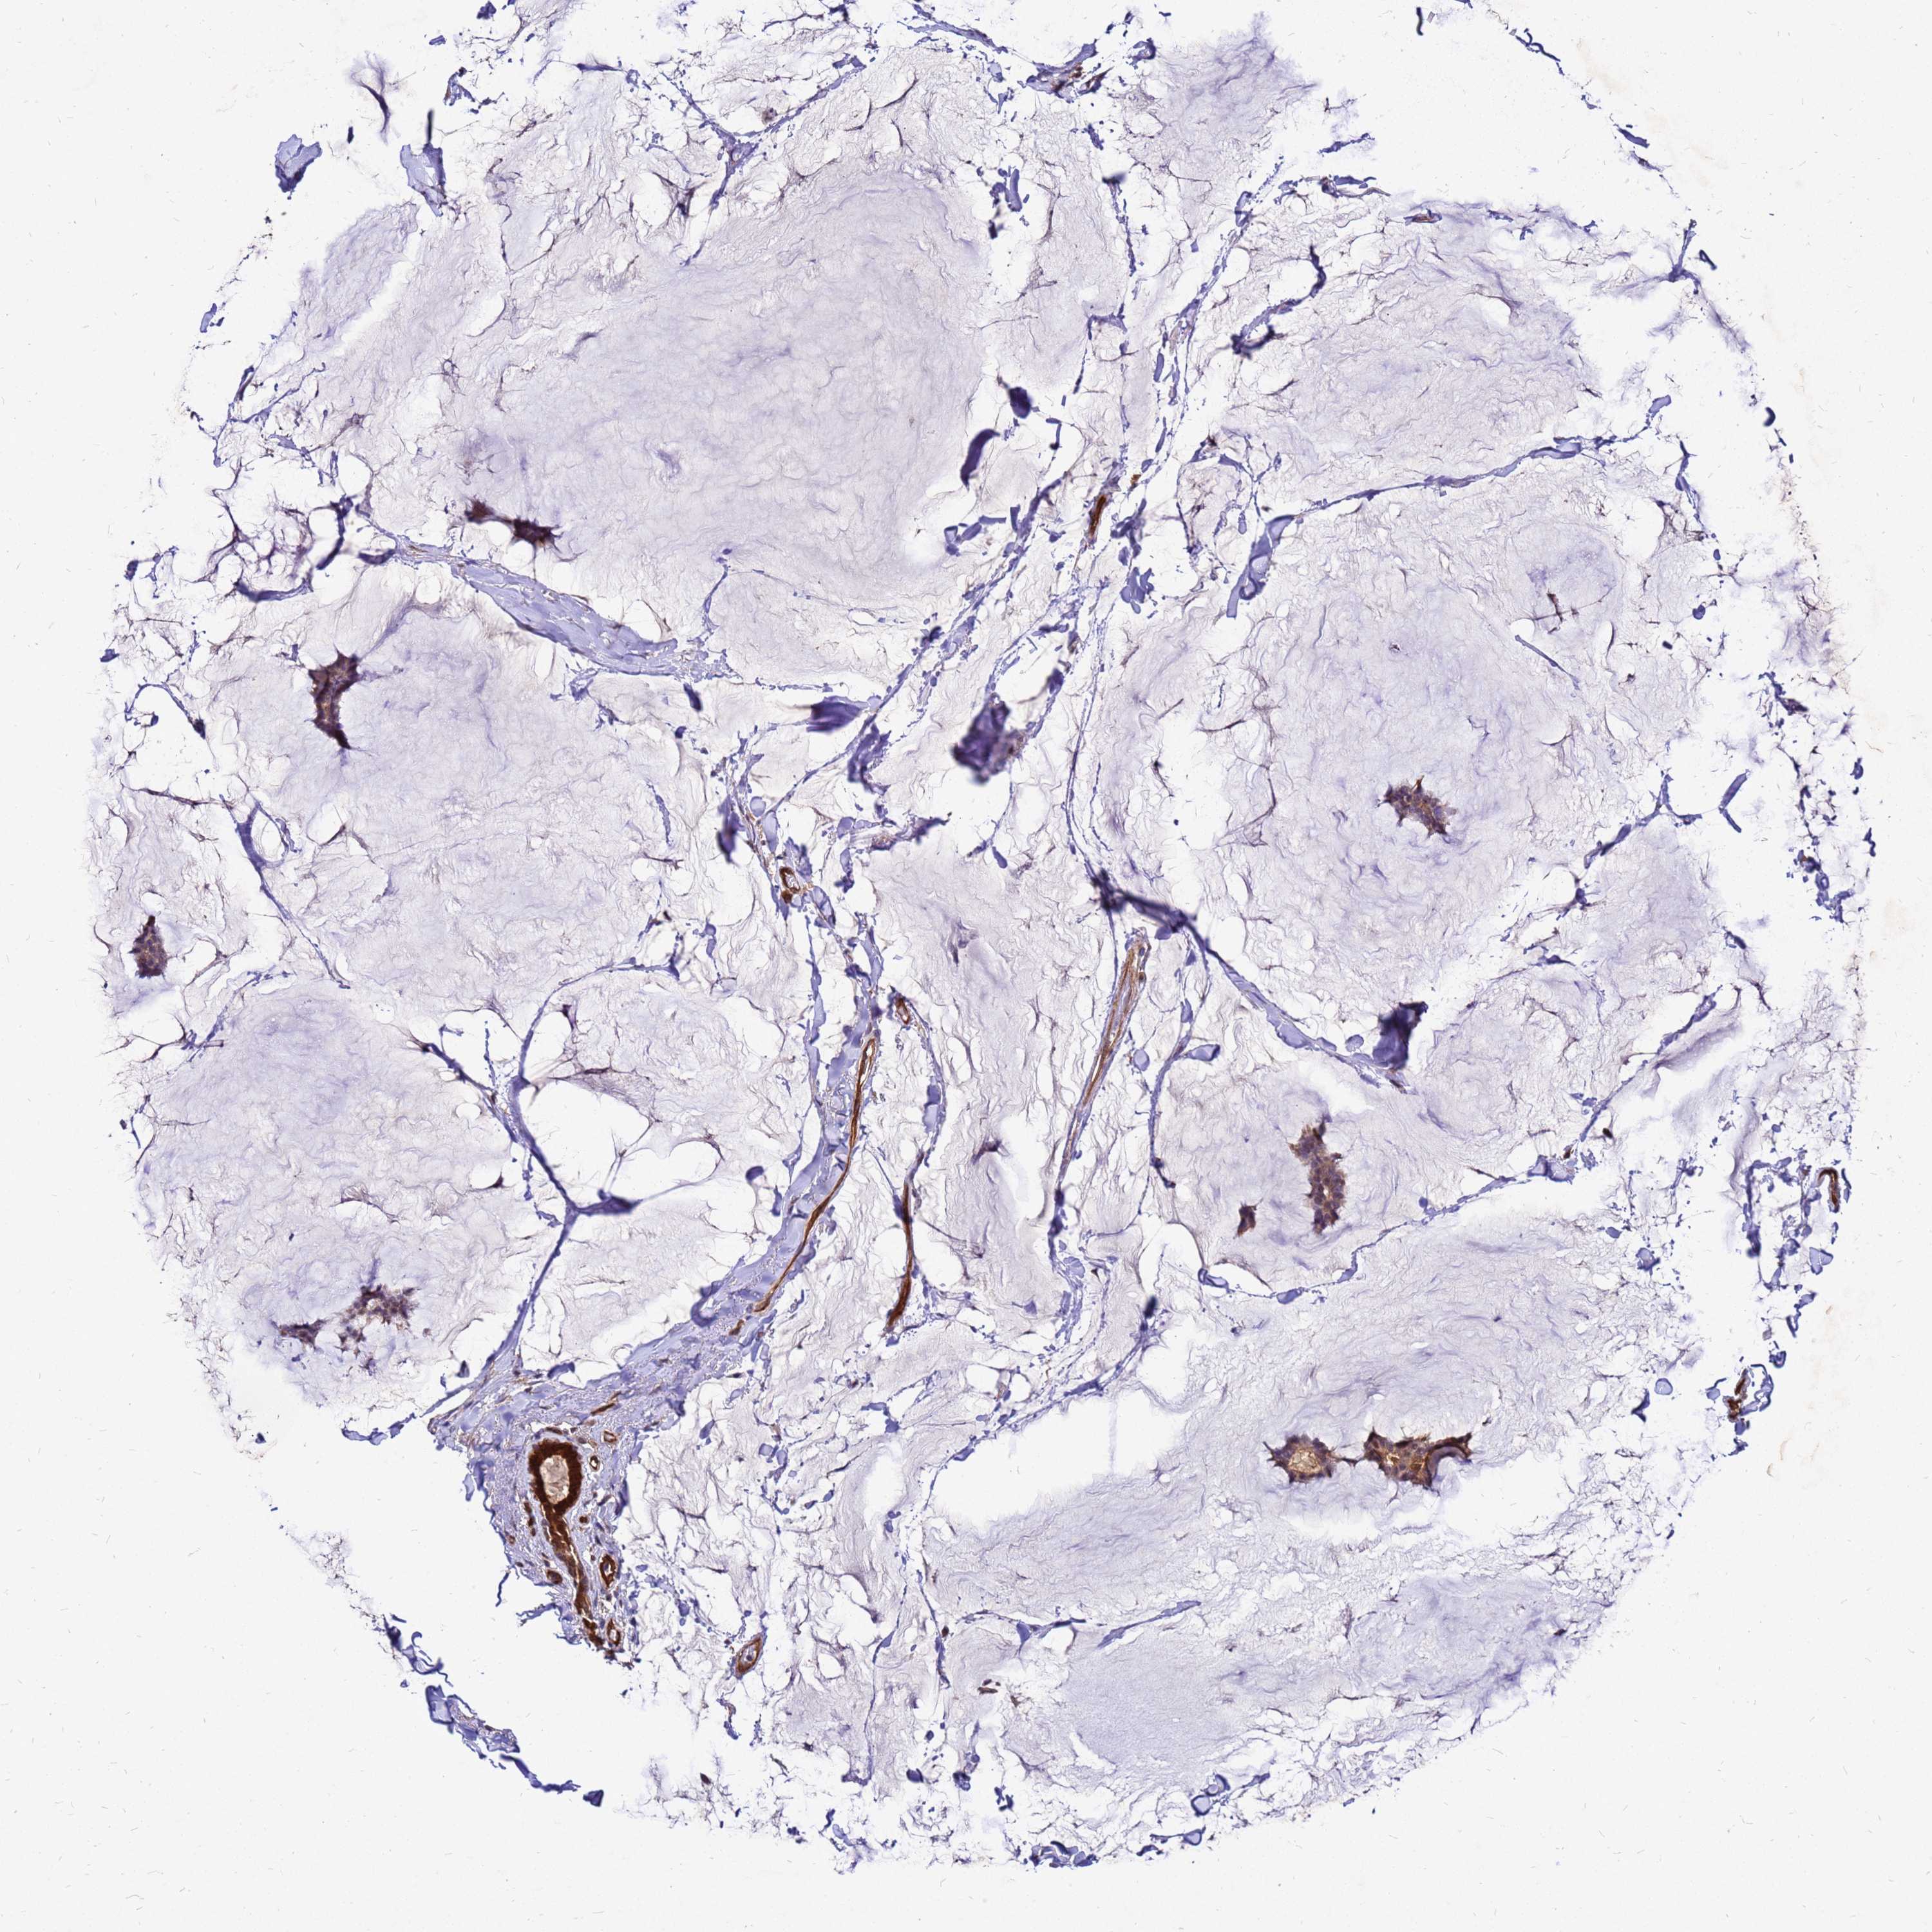

CANCER BREAST CANCER Show tissue menu

BRCA TCGA BRCA VALIDATION PROTEIN EXPRESSION

ANTIBODIES

AND

VALIDATION